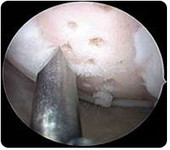

ChondroFiller Liquid (ein zellfreies Kollagenimplantat):

Bei dieser sehr schonenden arthroskopischen Operation wird ein zellfreies Kollagen in die Knorpeldefektzone injiziert und eine homogene Knorpeloberfläche hergestellt . Das Implantat besteht aus Kollagen Typ I, welches der Hauptbestandteil des körpereigenen Knorpels ist. Innerhalb weniger Minuten  bildet sich ein formstabiles Hydrogel, welches die Knorpeldefektzone vollständig ausfüllt. Aus der Umgebung wachsen körpereigene Knorpelzellen ein, welche schließlich zur Ausbildung eines knorpelähnlichen Regeneratsgewebes führt.

Zur Sicherung eines erfolgreichen Operations-Ergebnisses ist eine Teilbelastung von 6 Wochen postoperativ erforderlich.